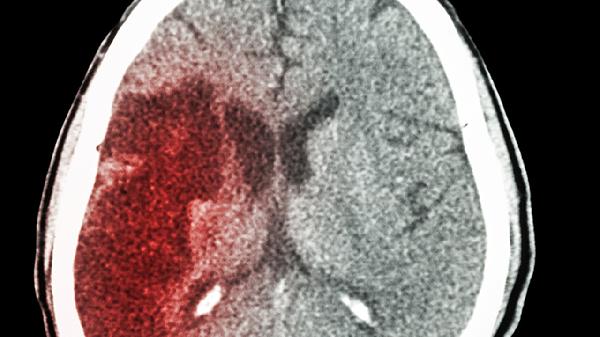

71岁老人突发脑梗,生活规律爱养花,医生叹息:只因睡觉爱做3事

看到邻居张大爷被救护车拉走时,阳台上那盆开得正艳的月季还在随风摇曳。这位每天准时晨练、饮食清淡的"养生模范",怎么突然就倒下了?主治医师查看病例后连连摇头:"问题就出在那些看似无害的睡前习惯上..."